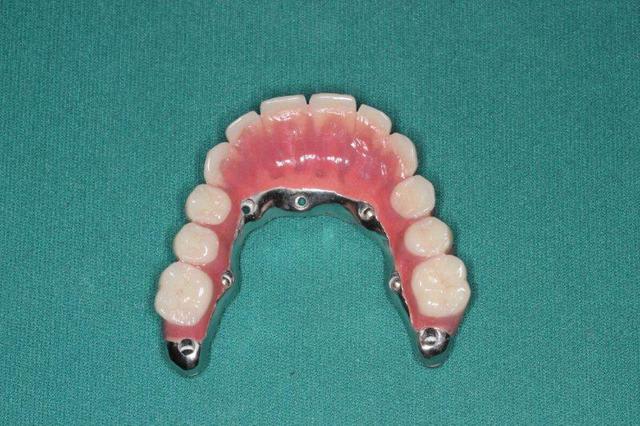

P'tite question, les vis qui tiennent la prothèse en place, sont des vis " plates", simple rainure.

C'est pas les vis les plus chiantes du monde à placer en bouche, ou c'est moi qui est trop malhabile ?

1. C est toi qui es malhabile... Rien de plus simple : tu mets ttes tes vis ds la puits, tu les recouvres d homéoplasmine pour les empêcher de tomber hors des puits, tu poses en bouche et tu passes ton tournevis ds homéoplasmine pour visser Très simple et très efficace :-))))

2. Effectivemeznt les plaques zygomatiques ont des émergences palatines mais au définitif j ai ôté les piliers prlongateurs de 3.5 mm et du coup même si sortie palatine plus aucun "débordement" du puits de vissage en dehors de l arcade...

3.Ca fait 18 mois que les implants sont en charge donc tu as déjà une idée mais de manière générale ça fonctionne aussi bien qu pilotis à la mandibule... Un petit coup de waterpik léger et qques bains de bouches suffisent à entretenir tout ça correctement

Regarde le provisoire de la MCI : les émergences des plaques au niveau molaires font des bombés hors arcades suite à la pose de piliers monobloc de hauteur 3.5 mm

On pose ces piliers car il faut pouvoir retrouver facilement les têtes d implants 72 h plus tard pour poser la prothèse de transition

1. l hexa te condamne à avoir un puits ds l axe exact du puits hexa... Les vis courtes et à fente te permettent de faire des puits légèrement courbe au niveau antérieur c e qui évite les vis trop gênantes vers vestibulaire qui te contraigent à faire des couronnes scellées sur armature primaire pour cacher les puits vestibulaires ...

Pépé a inventé le All on Seven...))))

Pcq ds ces cas là onne sait pas faire autrement

1. les palques ont une assisse énorme par rapport à 7 cylindres

2. la résorption centripède du maxillaire le rend trop petit pour en poser plus

De plus malgré le grand overjet , on a qd même un implant central qui soutient l arc incisif, même s il est 2 cm en arrière de la ligne des dents